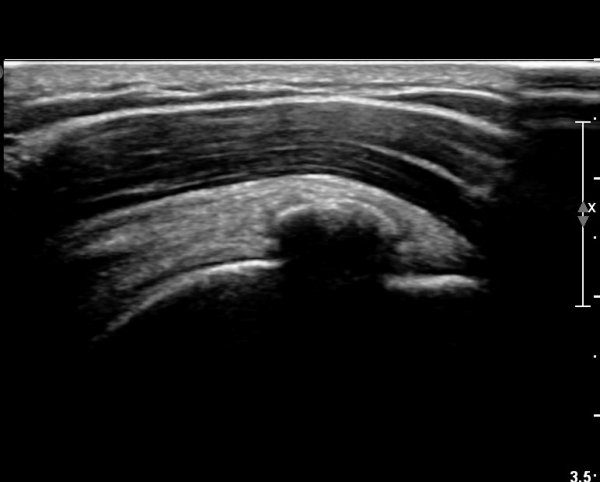

ÃÊÀ½ÆÄ ¼Ò°ß :  ±Ø»ó°Ç Á¾´Ü¸é°Ë»ç¿¡¼­ ÈĹæÀ½¿µÀ» º¸ÀÌ´Â °í¿¡ÄÚ ¼®È¸È­ µ¢¾î¸®°¡ °üÂûµÈ´Ù(»çÁø 1).

±Ø»ó°Ç Ⱦ´Ü¸é°Ë»ç¿¡¼­µµ ±Ø»ê°Ç³» ¼®È¸È­ µ¢¾î¸®°¡ °üÂûµÈ´Ù(»çÁø 2).